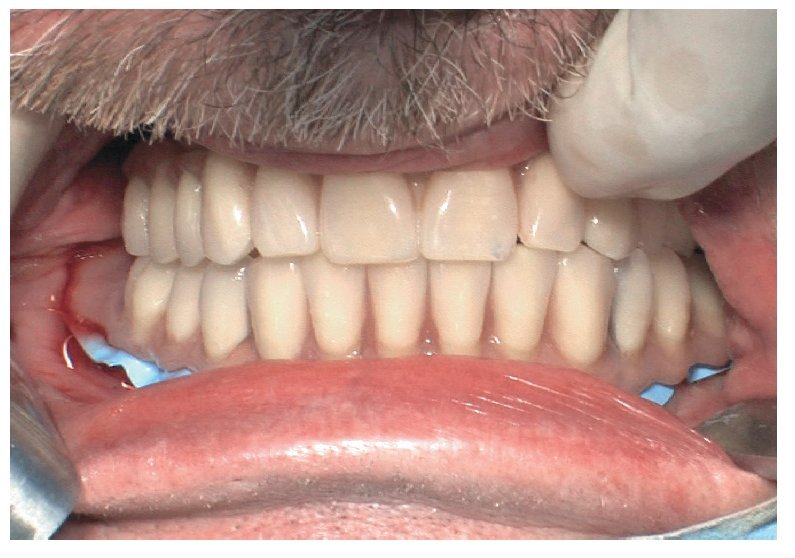

Fig. 73. Una vez concluida la intervención, tan sólo son necesarias pequeñas correcciones oclusales.

Pese a ello, es importante someter las estructuras a un control visual y mecánico, a fin de corregir eventuales discrepancias menores (figs. 99 a 102). A continuación se procede al montaje utilizando dientes protésicos prefabricados de composite (SR Phonares NHC, Ivoclar Vivadent, Ellwangen, Alemania), los cuales reproducen el tipo funcional correspondiente en virtud de sus propiedades morfológicas y estructurales y se integran armoniosamente en cuanto a su longitud dental (figs. 103 a 105). Durante la comprobación de las restauraciones protésicas, se evalúan clínica y radiológicamente ante todo la pasividad y la precisión del ajuste de la estructura. Acto seguido se lleva a cabo una comprobación de la oclusión y de la dimensión vertical, del estado de las prótesis y del tejido blando en la cresta alveolar, así como la verificación del espacio libre lingual, incluida la fonación, y el apoyo de los labios y las mejillas (figs. 106 y 107). También se debe comprobar la facilidad de higiene de la restauración de acuerdo con las habilidades manuales del paciente. A continuación se debe verificar la posición tridimensional de los dientes anteriores con los labios cerrados y durante la sonrisa, así como el aspecto global de la rehabilitación protésica.

Para la rehabilitación definitiva del paciente (figs. 116 a 124) deben comprobarse de nuevo todos los aspectos de la sesión anterior y debe procederse a la cementación de las prótesis. Son indispensables controles de seguimiento a corto plazo (al cabo de 1, 3 y 5 semanas) para el ajuste óptimo de la oclusión y la comprobación de la higiene oral con una prótesis que habitualmente ofrece aberturas de acceso periimplantares más estrechas que una prótesis provisional. Tres y seis meses después de la finalización del tratamiento se deben realizar controles clínicos, y una vez al año deberían llevarse a cabo sendos controles clínico y otro radiológico.

Figs. 118 a 120. La situación intraoral final.